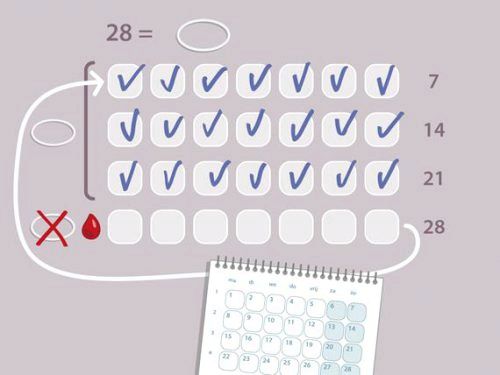

Після завершення циклу нову менструацію жінки очікують в середньому через 28 днів. Якщо з вашим організмом щось не так, то кровотеча почнеться значно раніше.